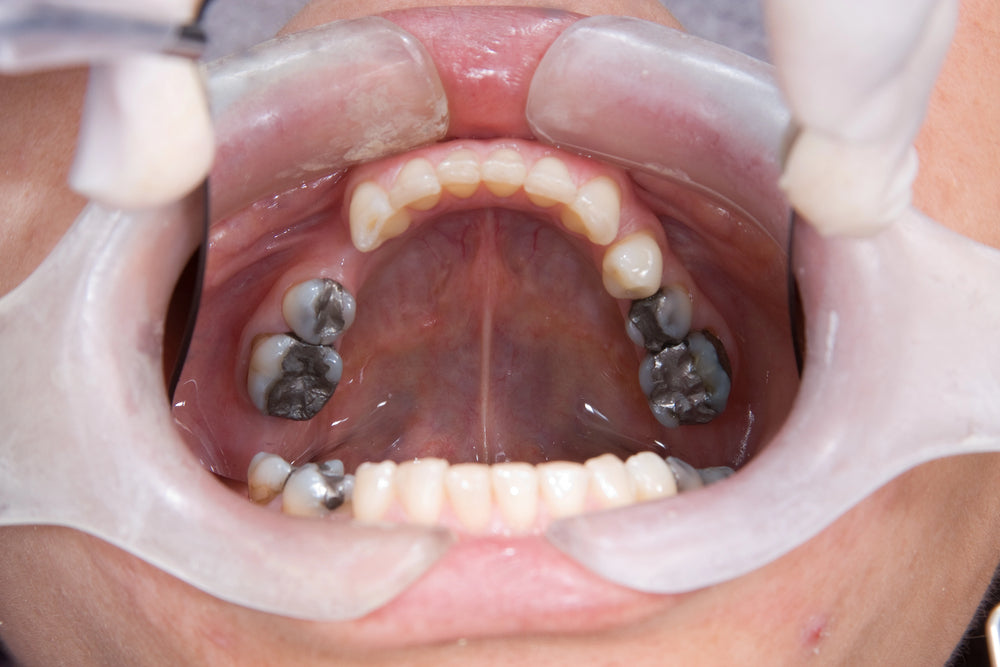

Full mouth reconstruction refers to an approach in which general or restorative dentists "overhaul" your smile for optimal oral health. It could involve therapeutic approaches designed to repair the damage, such as restoration of decayed or missing enamel , as well as replacement procedures designed to fill in missing spaces in your bite.

Restoring your mouth often includes both cosmetic and restorative procedures. Your dental specialists use services to address oral health challenges that affect not just how you look but your overall well-being as a whole. Your process might include different aesthetic and restorative procedures like oral surgery implants, ceramic crowns, or soft tissue grafting procedures - depending on what procedure you need.

Who needs a full mouth reconstruction?  Or when do you need full mouth reconstruction? Most people need a full-mouth reconstruction with many missing teeth, big dental fillings, or damaged teeth. This is especially beneficial for those with badly broken teeth as a result of the grind or injuries sustained in sports.